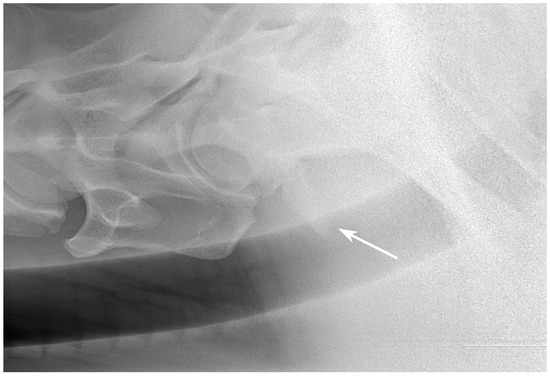

2.3. Radiographic Method

2.4. Classification System